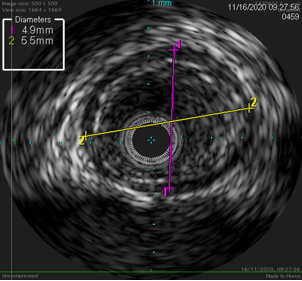

图:病变远心段(4.9+5.5mm)

图:支架形态规则处,有效面积24.1mm2,最小径 5.3mm,最大径 5.7mm。

图:支架局部不规整,最小径 3.7mm,最大径 5.7mm